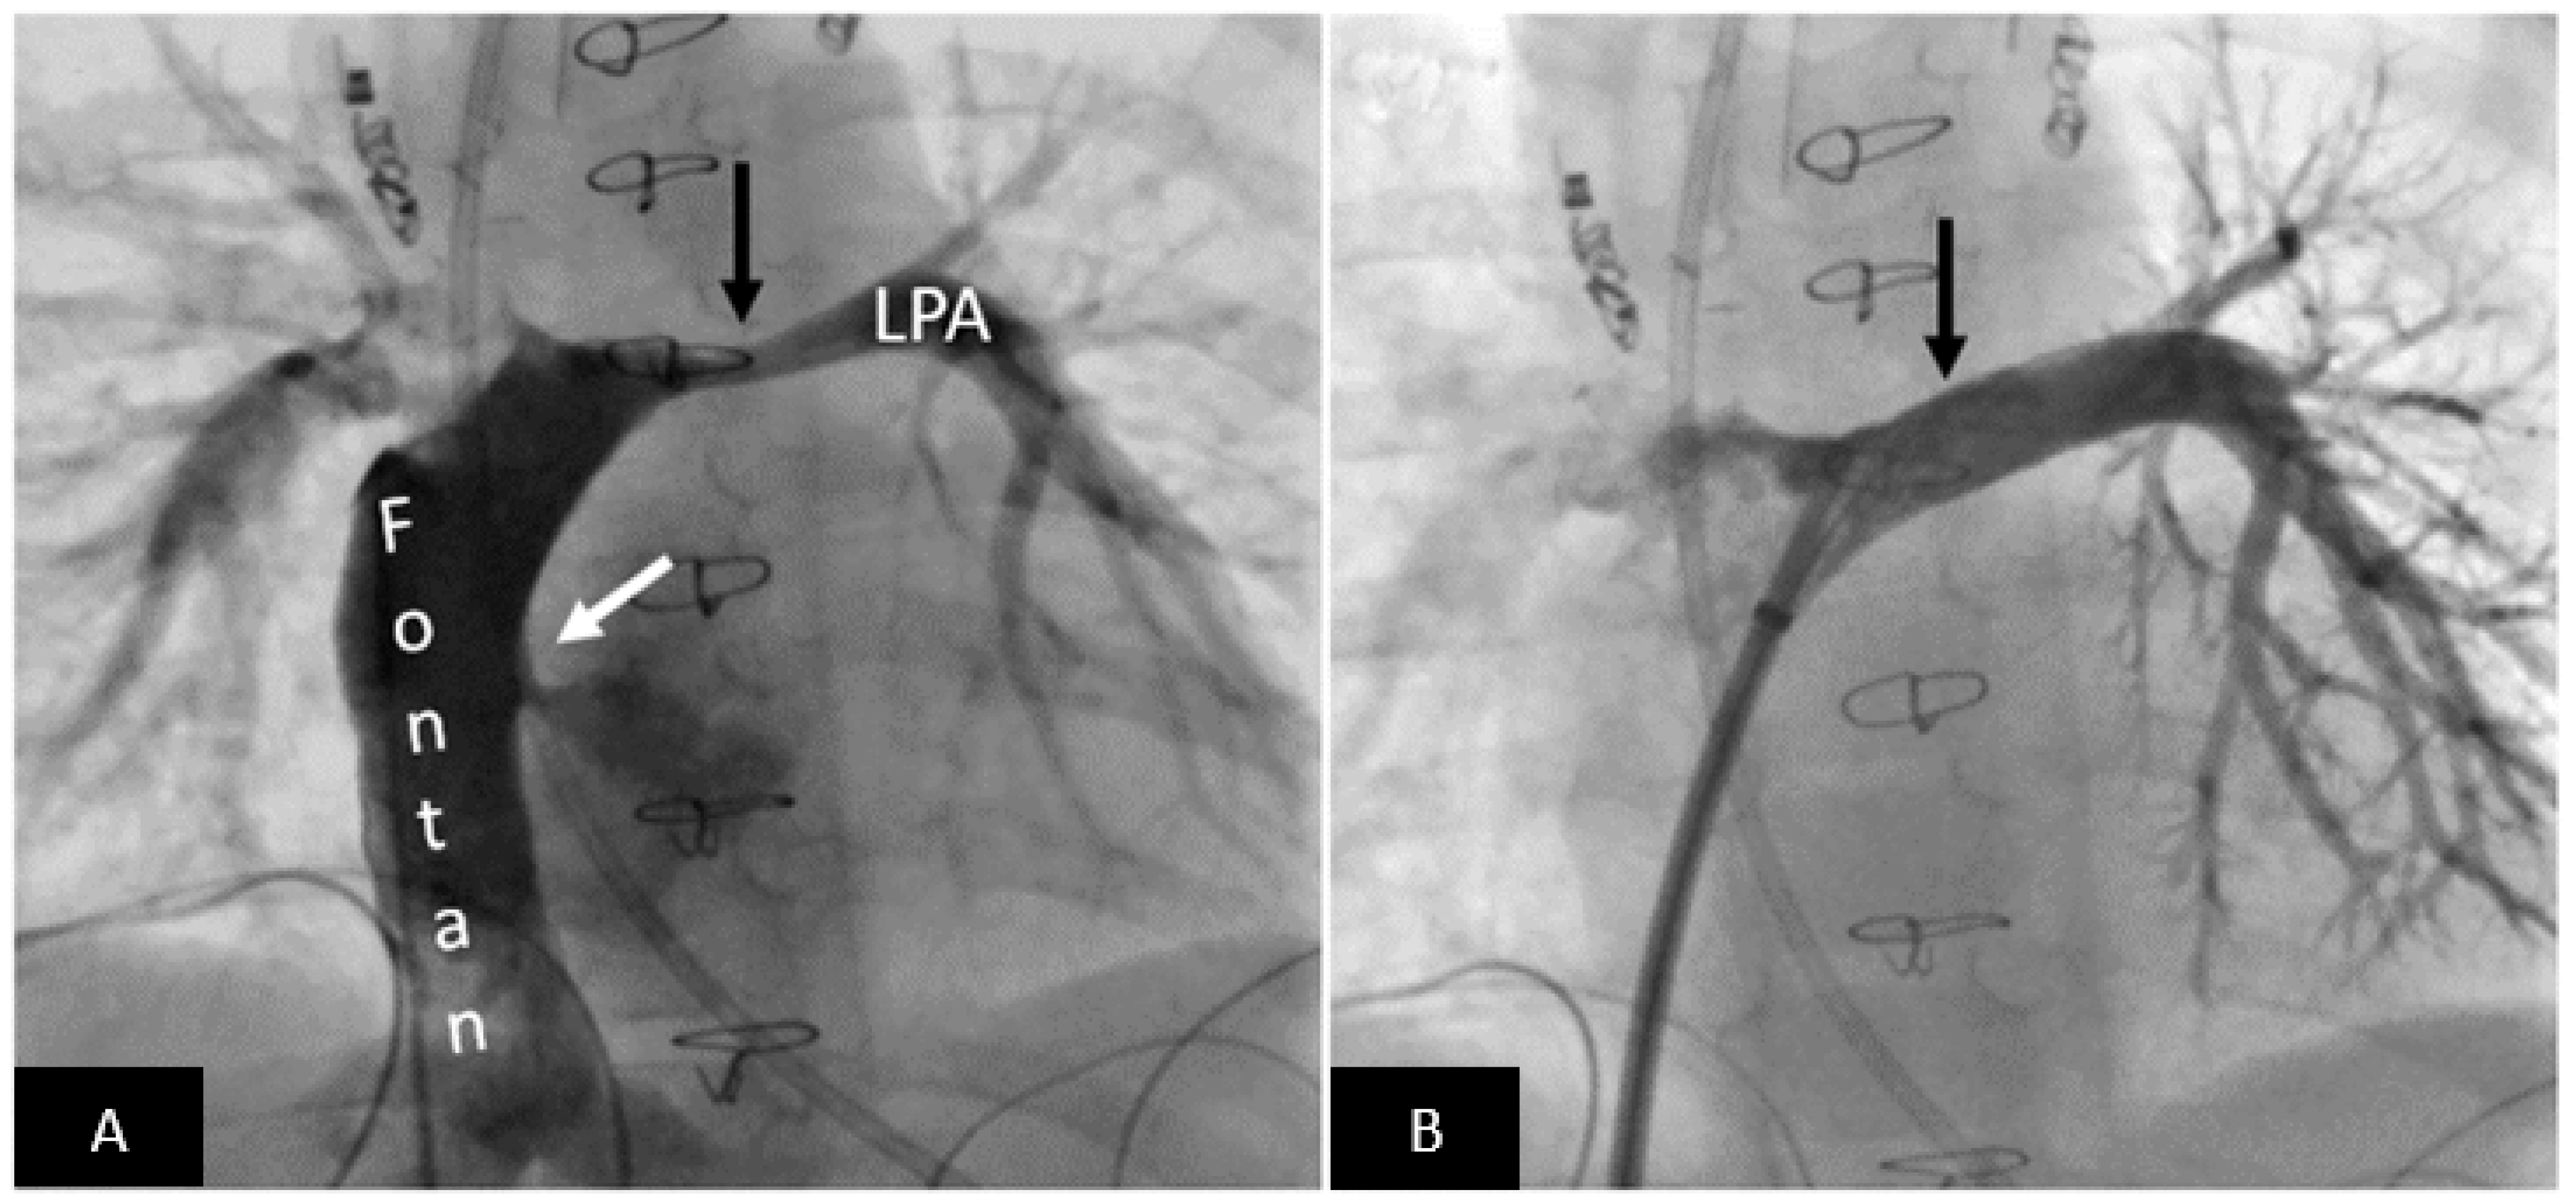

- Thakkar, A.N.; Chinnadurai, P.; Breinholt, J.P.; Lin, C.H. Transcatheter closure of a sinus venosus atrial septal defect using 3D printing and image fusion guidance. Catheter. Cardiovasc. Interv. 2018, 92, 353–357. [Google Scholar] [CrossRef] [PubMed] [Green Version]

- Velasco Forte, M.N.; Byrne, N.; Valverde, I.; Gomez Ciriza, G.; Hermuzi, A.; Prachasilchai, P.; Mainzer, G.; Pushparajah, K.; Henningsson, M.; Hussain, T.; et al. Interventional Correction of Sinus Venosus Atrial Septal Defect and Partial Anomalous Pulmonary Venous Drainage: Procedural Planning Using 3D Printed Models. JACC Cardiovasc. Imaging 2018, 11, 275–278. [Google Scholar] [CrossRef] [PubMed]